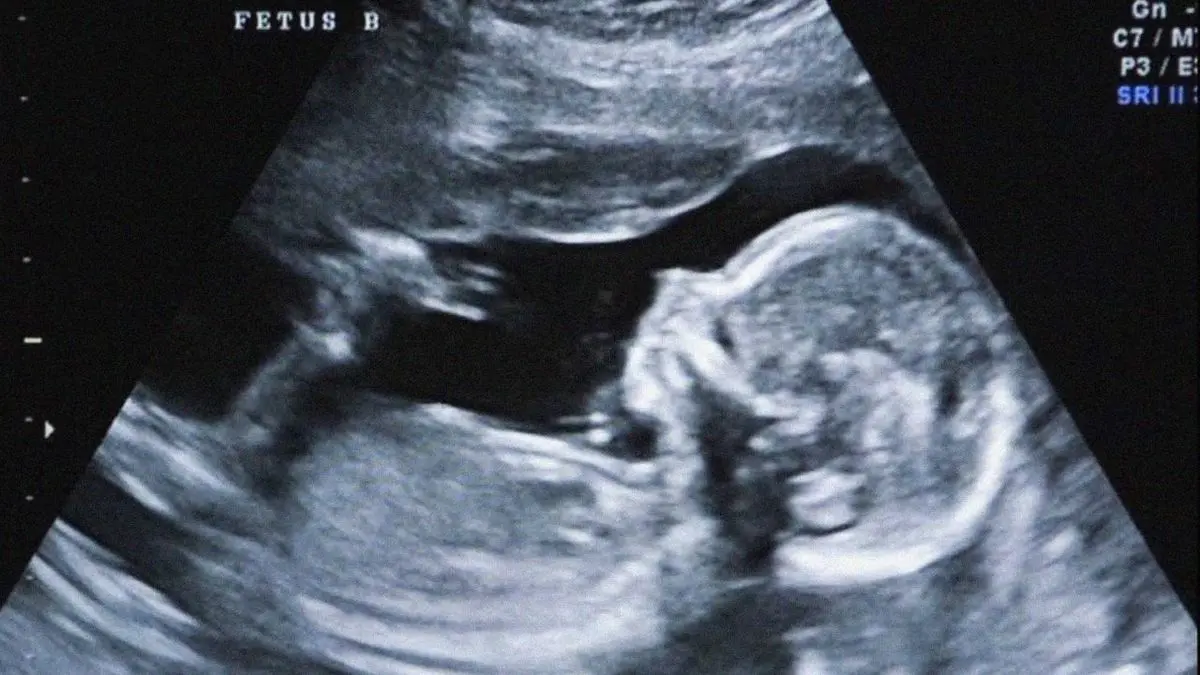

به گزارش دیده بان ایران؛  افشین استوار مدیرکل دفتر مدیریت بیماری‌های غیرواگیر وزارت بهداشت گفت: غربالگری جنین در دوران بارداری صد درصد اختیاری است، کادر بهداشت و درمان فقط به مادران توصیه می کنند درصورت تمایل برای انجام تست های اولیه غربالگری اقدام کنند.

سندرم دان و تریزومی های ۱۳ و ۱۸ شایع ترین ناهنجاریهای ژنتیکی هستند که امکان تشخیص آنها در ابتدای دوران بارداری به صورت همزمان وجود دارد.

احتمال بروز سندرم داون در هیچ سنی منتفی نیست و شناسایی افراد پرخطر تنها از طریق انجام مرحله اول غربالگری در تمام زنان باردار ممکن است.